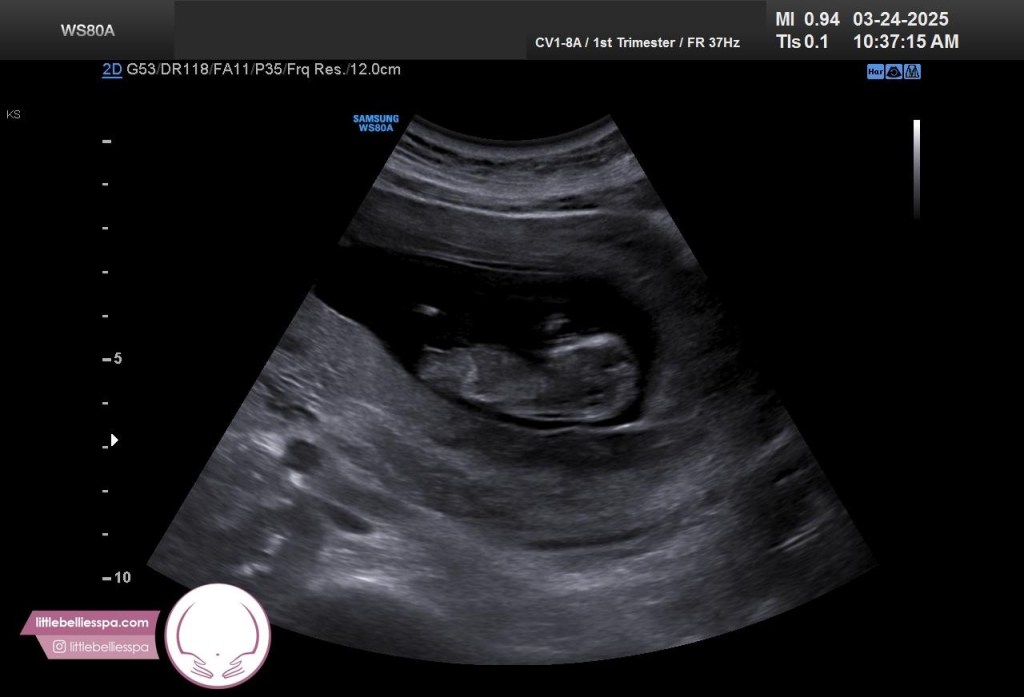

Gracias a la intervención de mi amada ex vecina, conocí a quien hoy ronca a mi lado. No, no es un cholulo (haciendo alusión a mi último post, jajajaja), pero vaya que entró con la misma fuerza en mi corazón. Se trata de mi ahora esposo, Guillotino. A la semana de salir con él supe, así como en capítulo de La Rosa de Guadalupe, que este caraqueño precioso iba a ser el papá de mis hijos (abajo la prueba, jajajaja). Y lo supe así porque, por primera vez en mi existencia, estaba con alguien con quien compaginaba en todos los puntos importantes de la vida, con quien moría de risa, la pasaba bom-ba, me entendía, me cuidaba y quien me llenaba de detalles increíbles, demostrándome siempre una certidumbre y convicción tal de querer estar conmigo que, verdaderamente, “he swept me off my feet”.

Mi cabeza olvidó por completo (cosa extraña) el tema… hasta que apareció este amable personaje en mi vida y me hizo volver a cuestionarme el tema. Con él, todo sí; “al shile” (o algo así pensé), dije: si es con este compa, 200% sí. Una vez que nos casemos descongelaremos los óvulos que tengo ahí listos y más na’. Además, a esta edad ya es muy complicado y no recomendable embarazarse porque #embarazogeriátrico (jajajajaja ¡qué poca madre! Btw)… y pues bueno, amad@ lectore, resulta que no se complicó tanto el pex, y pues en la sorpresa más grande de mi vida… vamos a ser papás.